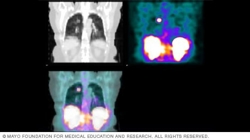

Exploración por tomografÃa computarizada por emisión monofotónica

Los resultados de la tomografÃa computarizada por emisión de fotón único pueden ser a color o en escala de grises. Las diferentes tonalidades o colores muestran qué células del cuerpo absorben más o menos cantidad del trazador radiactivo. Esta exploración implica imágenes de los riñones, el hÃgado y el bazo.

Un radiólogo o un especialista de atención médica con formación avanzada en medicina nuclear analizará los resultados de la tomografÃa computarizada por emisión de fotón único y los enviará a tu equipo de atención médica. Las imágenes de la exploración pueden revelar colores que le indican al equipo qué áreas del cuerpo absorbieron mayor cantidad de marcador radioactivo y qué áreas absorbieron menos. Por ejemplo, una imagen computarizada por emisión de fotón único del cerebro puede mostrar un color más claro donde las células cerebrales están menos activas y colores más oscuros donde las neuronas cerebrales están más activas. Algunas imágenes computarizadas por emisión de fotón único muestran escalas de grises en lugar de colores.